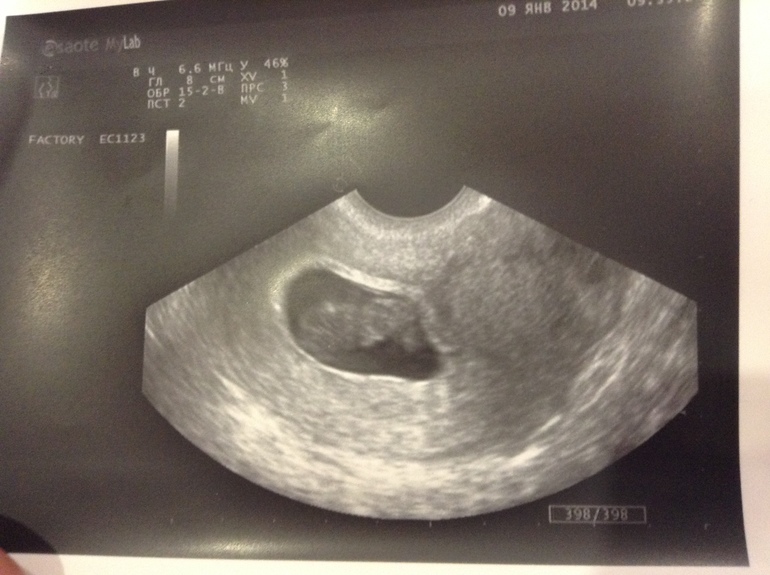

Узи 9-10 неделя

Привет девочки, сегодня была на узи, тонус в норме, малыш в порядке. ктр 22,8мм.

Немного волнуюсь,ктр соответствует 9 неделе, а вчера началась 10, но думаю к концу этой недели подтянемся. Врач сказала всё хорошо,а для меня это главное.

Выкладываю фотку))) Не разберу никак положение малыша, от радости у врача спросить забыла.Может вам понятнее?

Какая милаха)))) тьфу-тьфу, мне кажется голова слева и ножки под себя))))

По моим представлениям об эмбриончике головка слева! Легкой Вам беременности и родов!

Кажется лицом в низ и ножки под себя)))

прелесть!!! головкой в лево повернут смотрит личиком в низ!